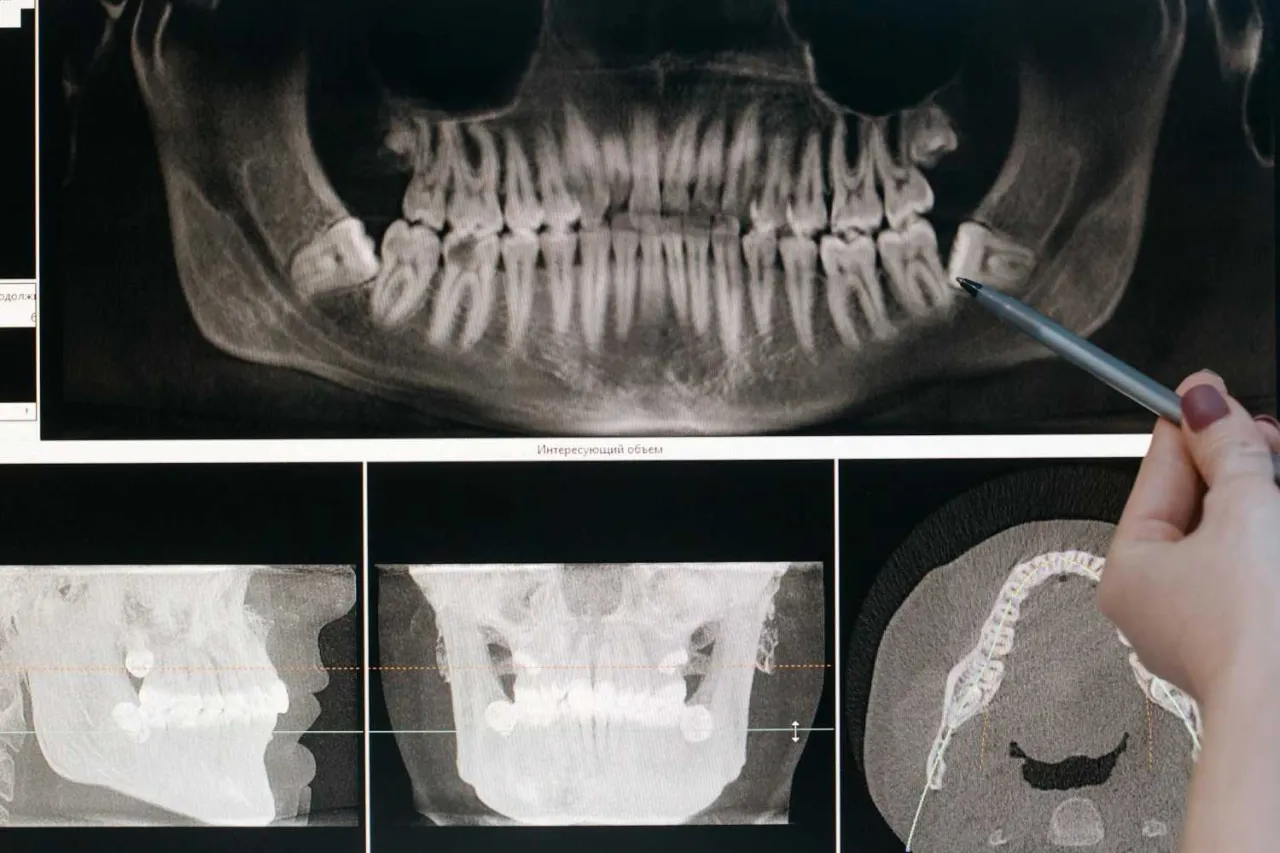

Ekstrakcja prosta dotyczy zębów, które są widoczne w jamie ustnej i nie mają skomplikowanych korzeni. Stomatolog używa specjalnych narzędzi (kleszczy i dźwigni), aby delikatnie rozchwiać ząb i usunąć go z zębodołu. Cały proces jest szybki i zazwyczaj nie wymaga nacinania dziąsła. Dłutowanie chirurgiczne, zwane też ekstrakcją chirurgiczną, jest konieczne w przypadku zębów zatrzymanych (np. ósemek, które nie wyrżnęły się w pełni), zębów niewyrżniętych, lub gdy korzeń zęba jest złamany i trudno dostępny. Zabieg ten jest bardziej inwazyjny wymaga nacięcia dziąsła, a czasem nawet usunięcia niewielkiego fragmentu kości, aby uzyskać dostęp do zęba. Po usunięciu zęba, rana jest zazwyczaj zaszywana, co wspomaga gojenie.